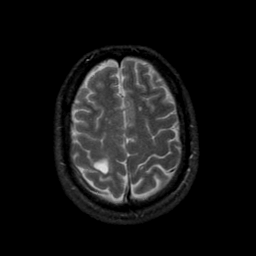

MR Study #9, April 14, 1991 -- Slice #40